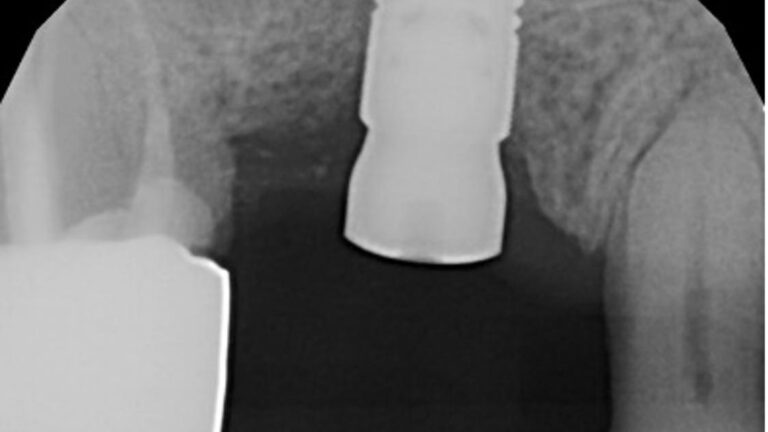

The patient presented on referral for identification of the implant in the #8 site and recovery of a fractured abutment and retained abutment screw which had lost its drive geometry.